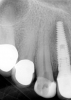

Fig 3. Preoperative maxillary left bicuspid.

Figure 3

The patient presented with temperature sensitivity and pain during mastication (Figure 3). Local anesthesia was delivered, and steps 1 through 4 were performed.